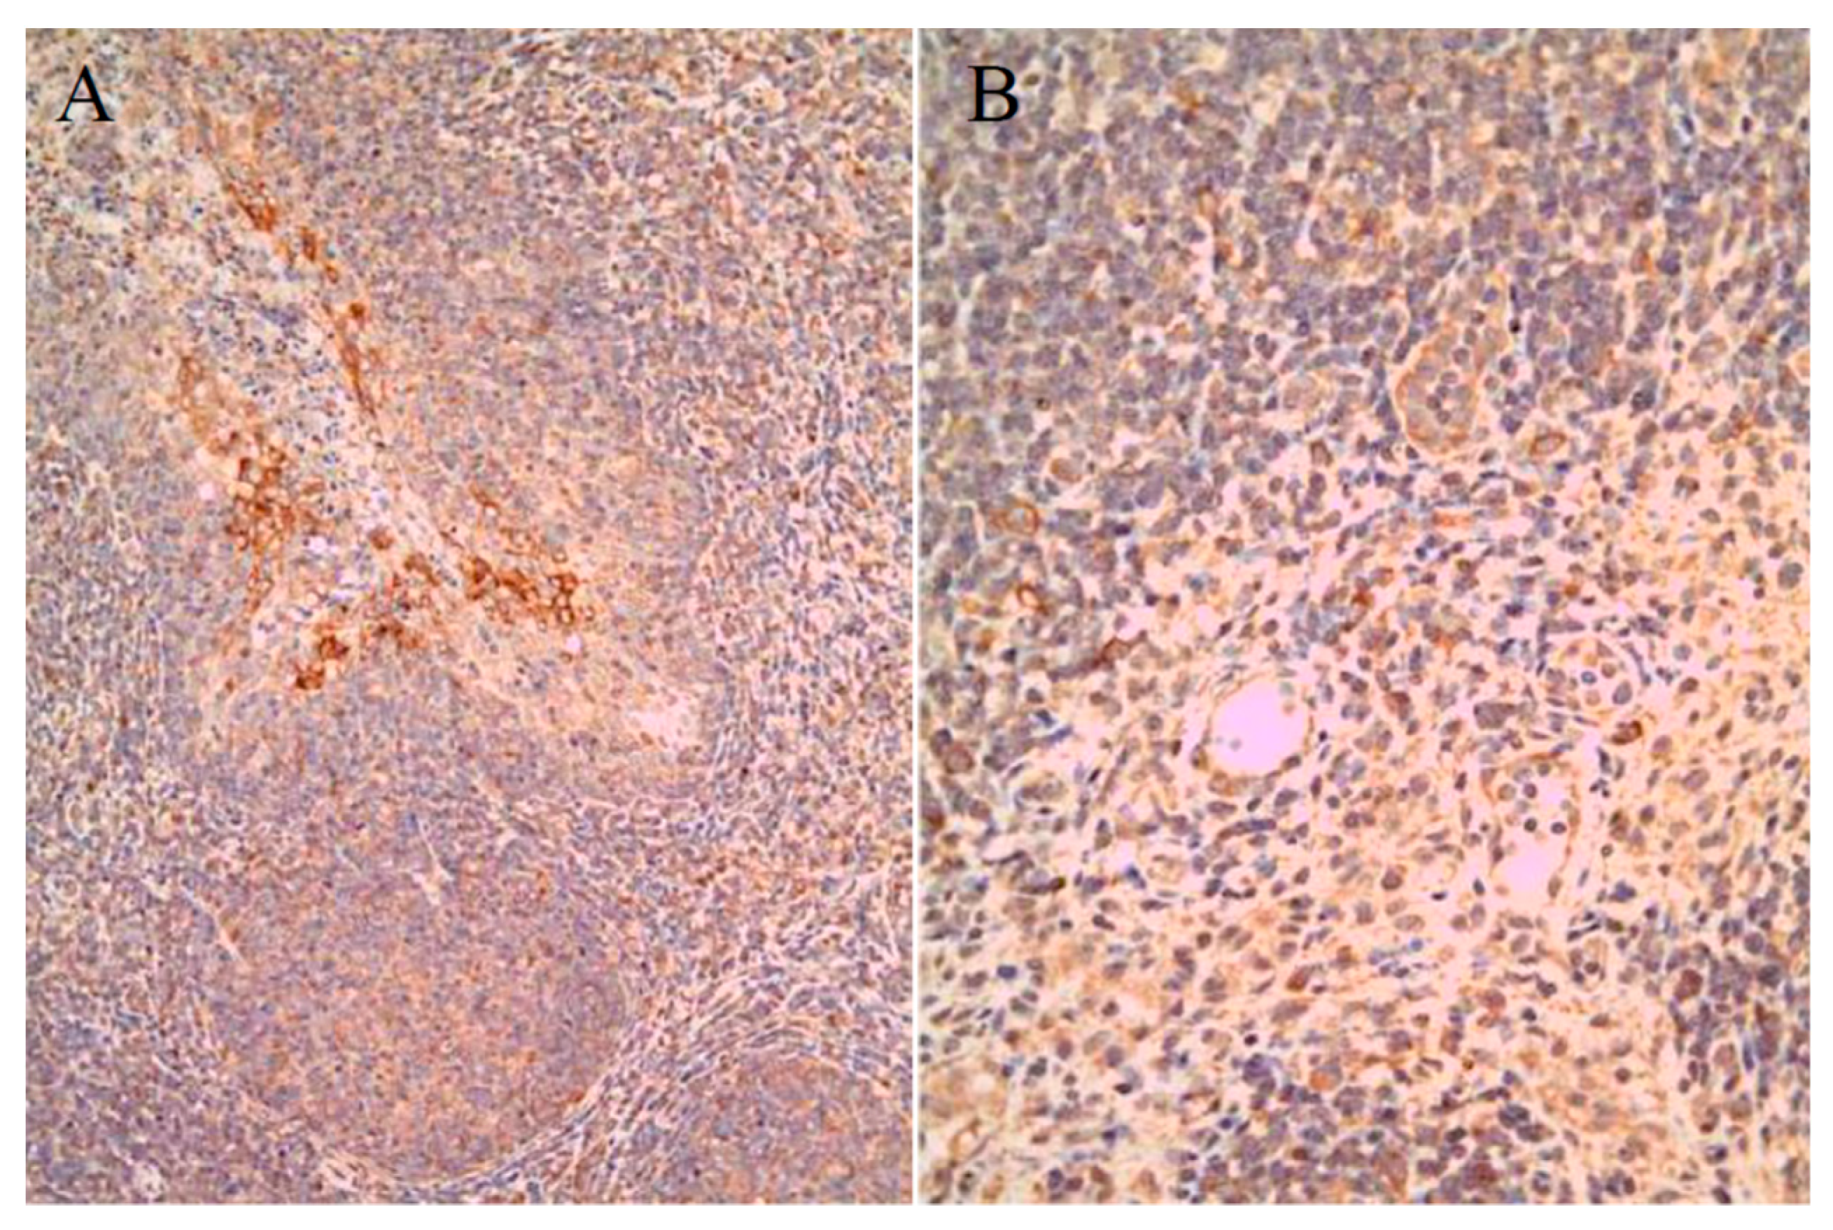

By IHC staining, viral antigens were detected within the organs of 10 group 1 SPF pigs, specifically in 7/10 (70%) tonsil, 1/10 (10%) spleen, 1/10 (10%) ileum, and 2/10 (20%) submandibular lymph node samples (Figure 3, Table 4). In addition, SPF pigs in group 2 were positive in 3/5 (60%) tonsil samples only, while samples from group 3 SPF pigs contained antigens in all samples, i.e., 5/5 (100%) tonsil samples, 2/5 (40%) spleen samples, and 1/5 (20%) ileum sample (Table 4).

Figure 3.

Immunohistochemical (IHC) results in SPF pigs. LOM antigens in the cryptal epithelium of tonsil (A) and solitary mono-nuclear cells in lymph node (B). Magnification × 200.